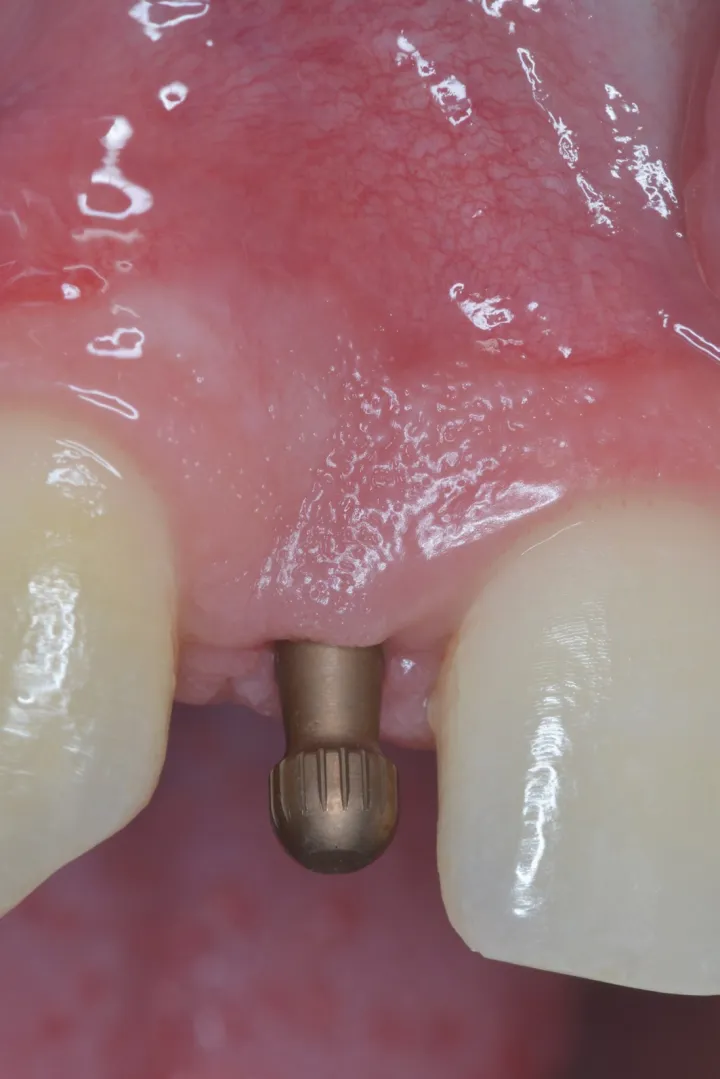

1 号病例 – Philippe RUSSE 医生(图 6 至 20)

18 岁男性患者,12、22 牙先天缺失。近远中间隙减小,种植区唇颊侧、牙槽嵴顶上方存在凹陷,适合采用小直径种植体。

图 8 :种植位点。

图 9 :植入 Axiom® 2.8 种植体。

图 10 :植入种植体。